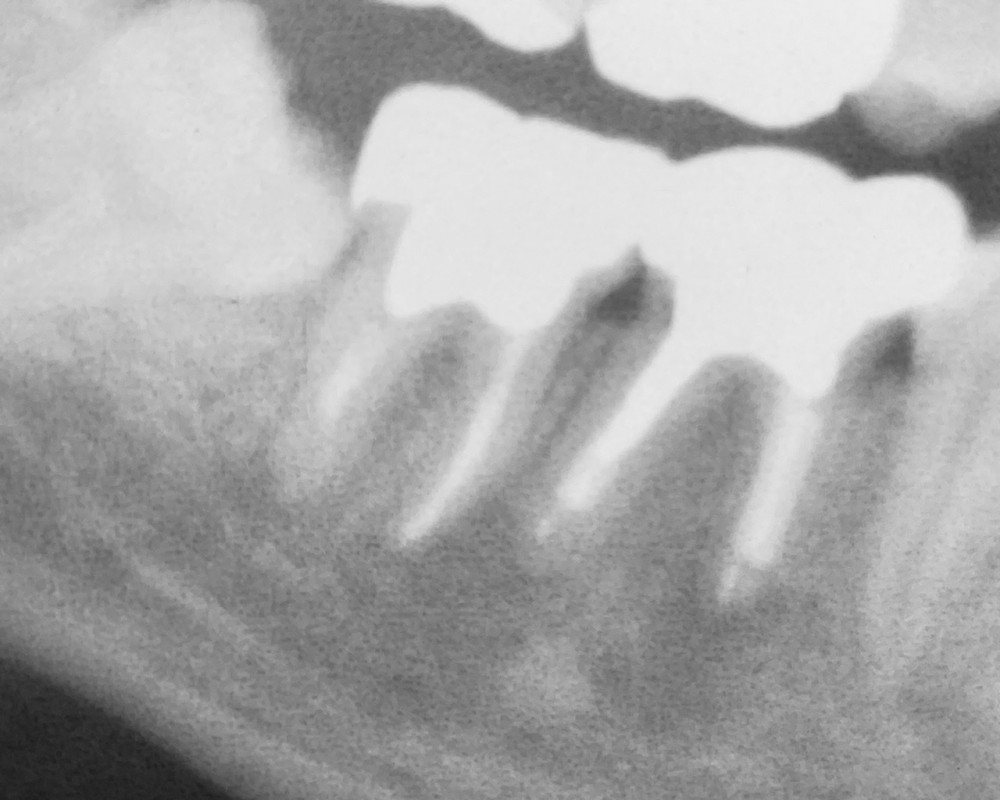

そして、当院での治療後、数ヶ月して撮影したエックス線写真がこちらです。(令和5年6月に撮影したものです。)

根管内にお薬が綺麗に充填され、歯根先端の歯槽骨が新しく作られているのが確認できます。